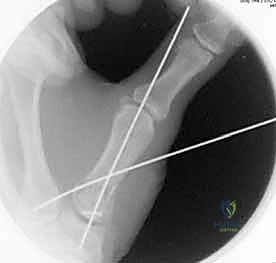

1. الرد المغلق والتثبيت عبر الجلد بالإبر (CRPP - Closed Reduction and Percutaneous Pinning)

هذا الإجراء هو الخيار المفضل لكسور "بينيت" التي يمكن إعادتها لمكانها بدون فتح جراحي كبير.

* الخطوات: يتم إجراء العملية تحت التخدير الموضعي أو الكلي. باستخدام جهاز الأشعة السينية المباشر في غرفة العمليات (C-arm Fluoroscopy)، يقوم البروفيسور هطيف برد الكسر إلى مكانه المثالي.

* بعد ذلك، يتم إدخال إبر معدنية دقيقة (K-wires أو Kirschner wires) عبر الجلد مباشرة لتثبيت قاعدة المشط الأول بالعظم المربعي، وأحياناً بالمشط الثاني لزيادة الاستقرار.

* الميزة: شقوق صغيرة جداً، ألم أقل، وشفاء أسرع. يتم إزالة هذه الإبر عادة في العيادة بعد 4 إلى 6 أسابيع.